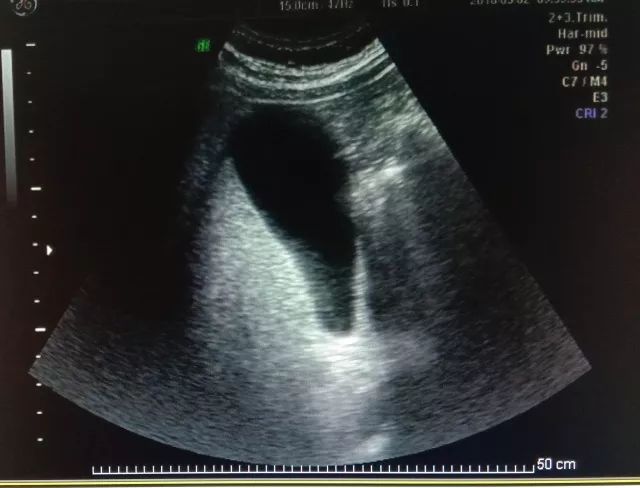

为什么孕期需要做4-5次超声检查,算不算过度医疗?

孕期长达40周,不同孕期进行超声检查有不同用途,早孕期超声用来判断胚胎着床位置是否正常,以及是否有心管搏动;12周左右行NT检查测量胎儿颈背部皮肤厚度,是为了早期发现存在染色体异常可疑的胎儿;23周系统彩超,即大排畸,是对胎儿各个系统是否存在异常,畸形等进行大范围排查;现在,我们常建议孕妇在28周做小排畸彩超,目的是动态观测胎儿的生长情况,同时对结构进行补充扫查,因为有些疾病随胎儿孕周增大慢慢表现出来,比如膈疝;在分娩之前,孕妇做最后一次彩超,为产科医生提供胎儿大小,胎位,胎盘成熟度,羊水量等数据,做好分娩准备。所以说,对孕妈妈进行的这些彩超检查都是必要的,并不是过度医疗。